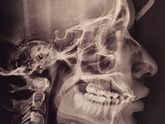

11 февраля 2017 20:59 Вы удаляли зуб мудрости после снятия брекетов,и как сильно на этом настаивал ваш врач?У меня даже нет зубов мудрости,а ортодонт вовсю кричит,что надо его удалить или иначе будет все в прежнем состоянии?